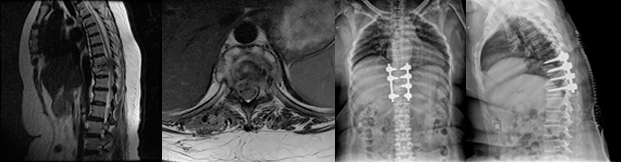

The patient usually presents with cosmetic disfigurement like uneven shoulders or waistline, a prominent chest wall on one side, hump on one side of the back, etc. These are the most common findings in a child with idiopathic scoliosis. It should be remembered that scoliosis other than idiopathic may present with weakness of arms or legs and loss of urinary control. A child with severe deformity may have difficulty in breathing due to impaired chest wall function.

Following an extensive assessment, the doctor will decide to treat the condition with bracing or surgery depending on age, severity of curve, underlying disease processes and degree of breathing difficulty.

The treatment varies for each type of deformity. For idiopathic scoliosis surgery is usually done when the curve exceeds 40 degrees or in rapidly progressing curves. For other types of deformities surgery is done when child presents with pain, limb weakness, bladder disturbance and has achieved sufficient age and weight to sustain the operative procedure.

Posterior Fusion

Posterior fusion with instrumentation is the most common operation done for idiopathic scoliosis. In posterior fusion the spine is operated on from behind with an incision straight down the back. Various types of rods, hooks, wires or screws are used to partially straighten the spine and hold it fast while the bone fusion occurs.

Anterior Fusion

In anterior fusion, the spine is operated on from the front, or side. Anterior fusion is used in some special instances of idiopathic scoliosis. An incision is made along a rib and/or down the front of the abdomen to obtain access to the front of the spine. Bone graft from the hip, rib or bone bank is used for the fusion. Screws and washers attached to a rod may be used to straighten the spine.

Combined (Anterior and Posterior Fusion)

Some special cases of spinal deformity require both an anterior (front) and posterior (back) operation. Usually these can be done on the same day, but sometimes must be done at separate operations spaced 1-2 weeks apart.

These surgeries are performed under intraoperative neuro-monitoring system which gives continuous input to the surgeon about the function of the spinal cord throughout the surgery. This enables safe application of screws into the spine, bony correction and straightening of the deformed spine without risks of injuring the spinal cord.